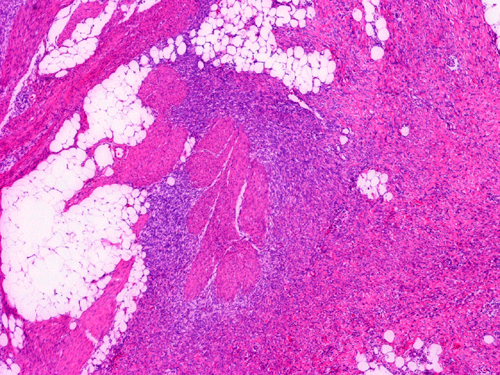

The excised mass is composed of an intermingled arrangement of mature adipose tissue, densely packed primitive spindle cells with small amount of cytoplasm, and mature appearing spindle cells with substantial amount of cytoplasm that gives the appearance of smooth muscle (Panel  A). Abrupt transition between the three elements are common (Panel B). The densely packed, small primitive spindle cells have elongated, cigar-shaped nuclei with amphophilic cytoplasm. Pleomorphism and mitotic figures are not seen. A small number of lymphocytes are present among these cells (Panel C). In areas with appeance of smooth muscle, the cells have elongated, sometime wavy nuclei without significant pleomorphism or mitosis (Panel D). Areas with thick, wavy collagen fibers admixed with benign appearing spindle cells are also present (Panel E and F) and some of these areas are more loosely packed than the other areas which may mimic the appearance of a neurofibroma. In contrast to other areas, these collagenous areas merge imperceptibly with the more cellular areas. In some of the densely packed spindle cell areas, there are small packets of loosely packed cells that give a myxomatous morphology on high magnification (Panel G and H).

Histologically, FHI has a triphasic organoid pattern with three distinct types of tissues: fibrous tissue; primitive mesenchyme appearing tissue; and mature adipose tissue. The fibrous tissue consists of well-differentiated spindle cells of fibroblastic/ myofibroblastic appearance admixed with a variable amount of collagen fibers. The dense fibrous tissue may form a fibrous core or at the center of the lesion. The primitive mesenchyme appearing tissue consists of sheets of undifferentiated spindle cells or stellate cells with an amphophilic and inconspicuous cytoplasm. Often these cells arrange in a concentric pattern and form whorls or characteristic ball-like structures in a vascular, mucoid matrix. Scattered lymphoid cells and extravasated erythrocytes are common findings in these areas.  The relative proportions of these three components vary in different cases greatly.